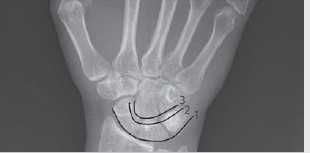

IV. Carpal Arcs

Gilula’s lines are three arcs drawn on the PA view, which are used to assess the alignment of the carpal bones (► Fig. 3.4):

First arc—smooth curve outlining the scaphoid, lunate, and triquetrum.

Second arc—the distal concave surfaces of the same bones.

Third arc—proximal curvature of the capitate and hamate.

Break in arc indicates fracture, ligamentous injury, and lunate/perilunate dislocation.